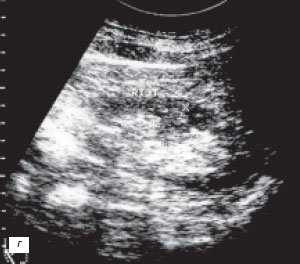

4. УЗИ при дефекте соединения паренхимы почки:

• Эхогенная линия, проходящая косо от передневерхней к задненижней поверхности почки (соединительная линия)

• Периферическая клиновидная эхогенность вдоль плоскости слияния почечек (вследствие инвагинации околопочечной жировой клетчатки)

о Лучше определяют на УЗИ в связи с более высоким пространственным разрешением и мультипланарной визуализацией

о Лучшей визуализации достигают в парасагиттальных проекциях

(Слева) УЗИ, косая сагиттальная плоскость сканирования правой почки: у мужчины 55 лет выявлена зона эхогенности треугольной формы на передней поверхности верхнего полюса, продолжающаяся в синус почки, что соответствует дефекту паренхиматозного соединения.